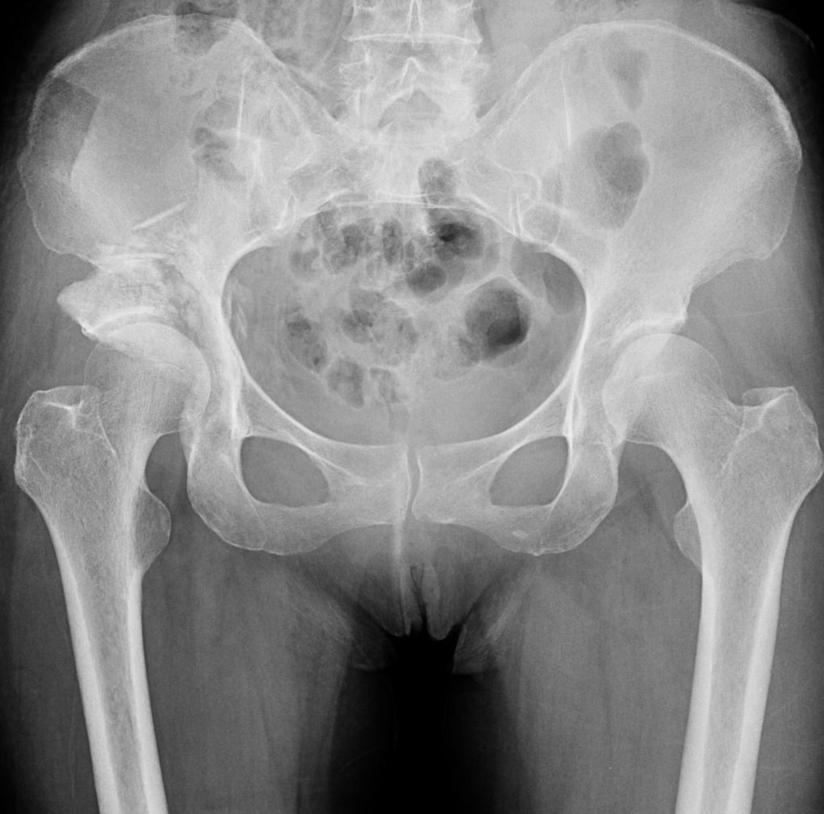

股骨头坏死 我国有了 经济实用型 原创新术式 科技新闻 中国科技网首页